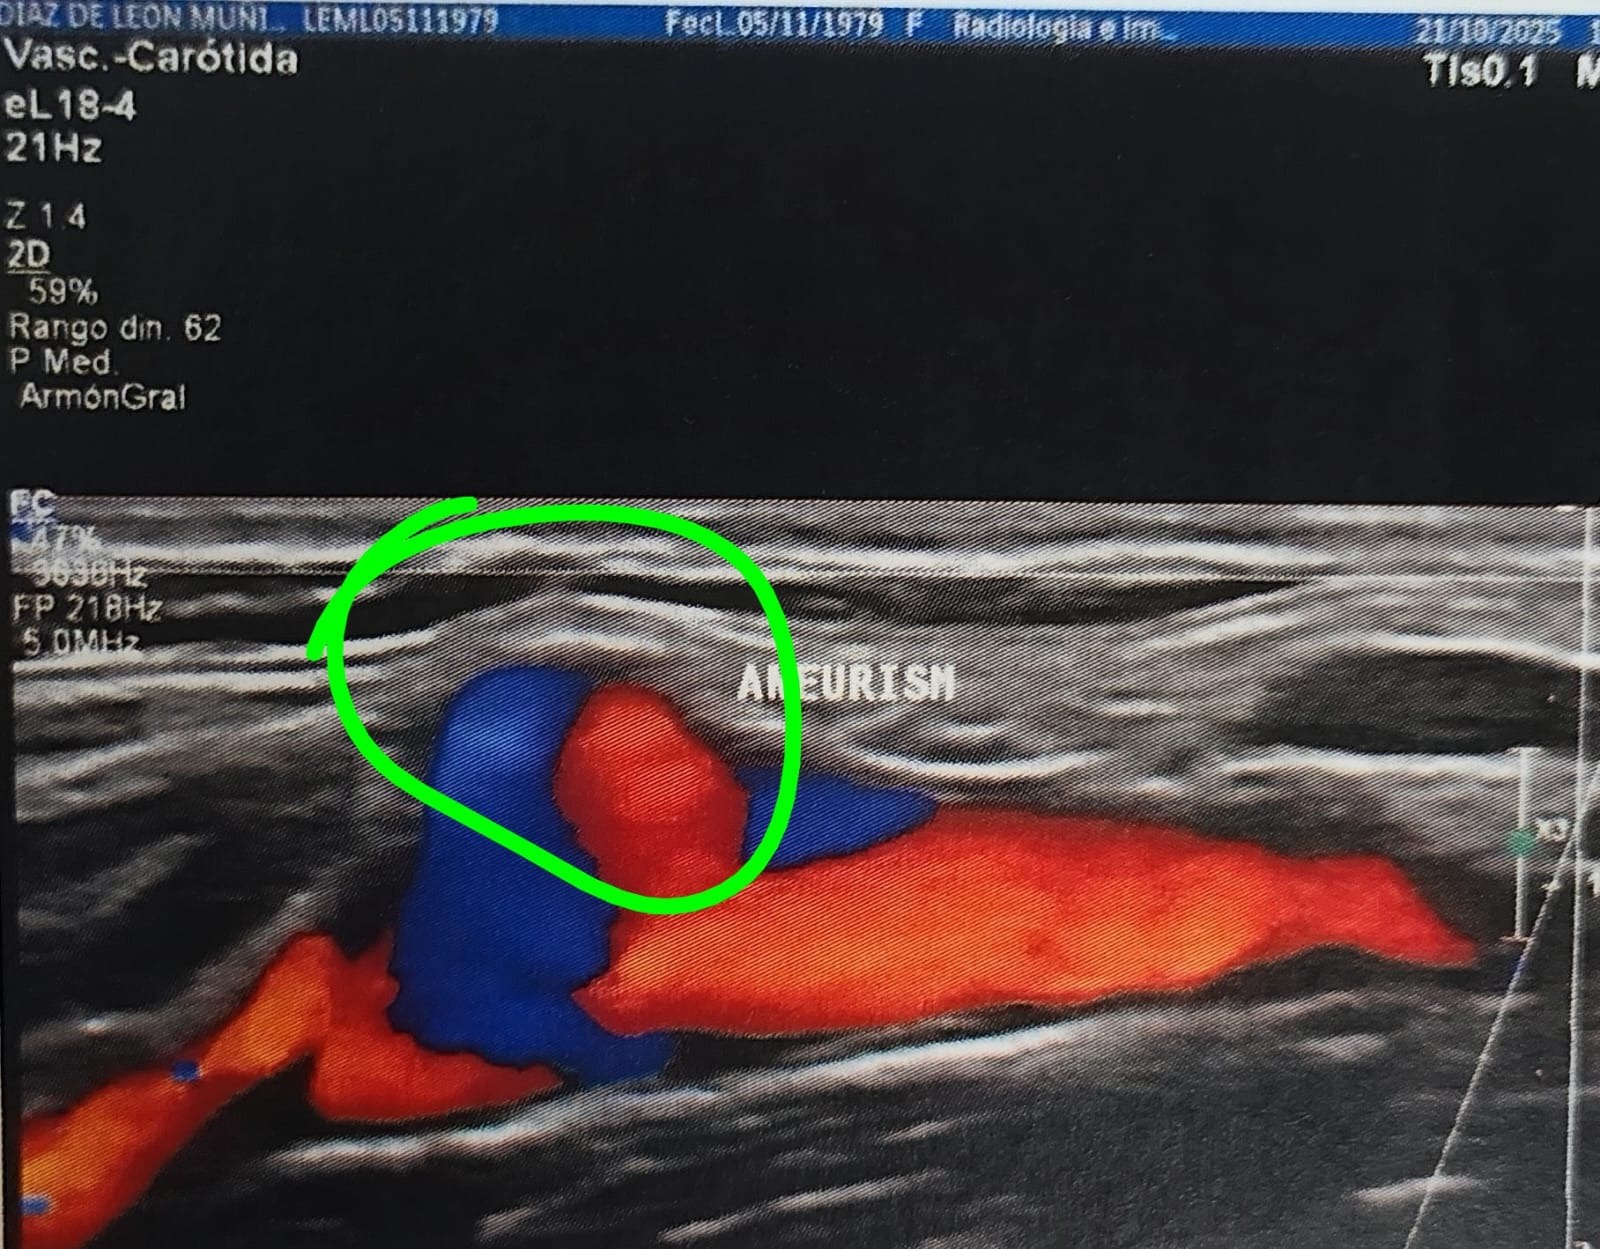

Mi esposa, Leslie Díaz de León Muñiz, fue diagnosticada con un pseudoaneurisma carotídeo, una condición extremadamente grave. Los médicos han sido claros: en cualquier momento puede romperse y provocarle la muerte.